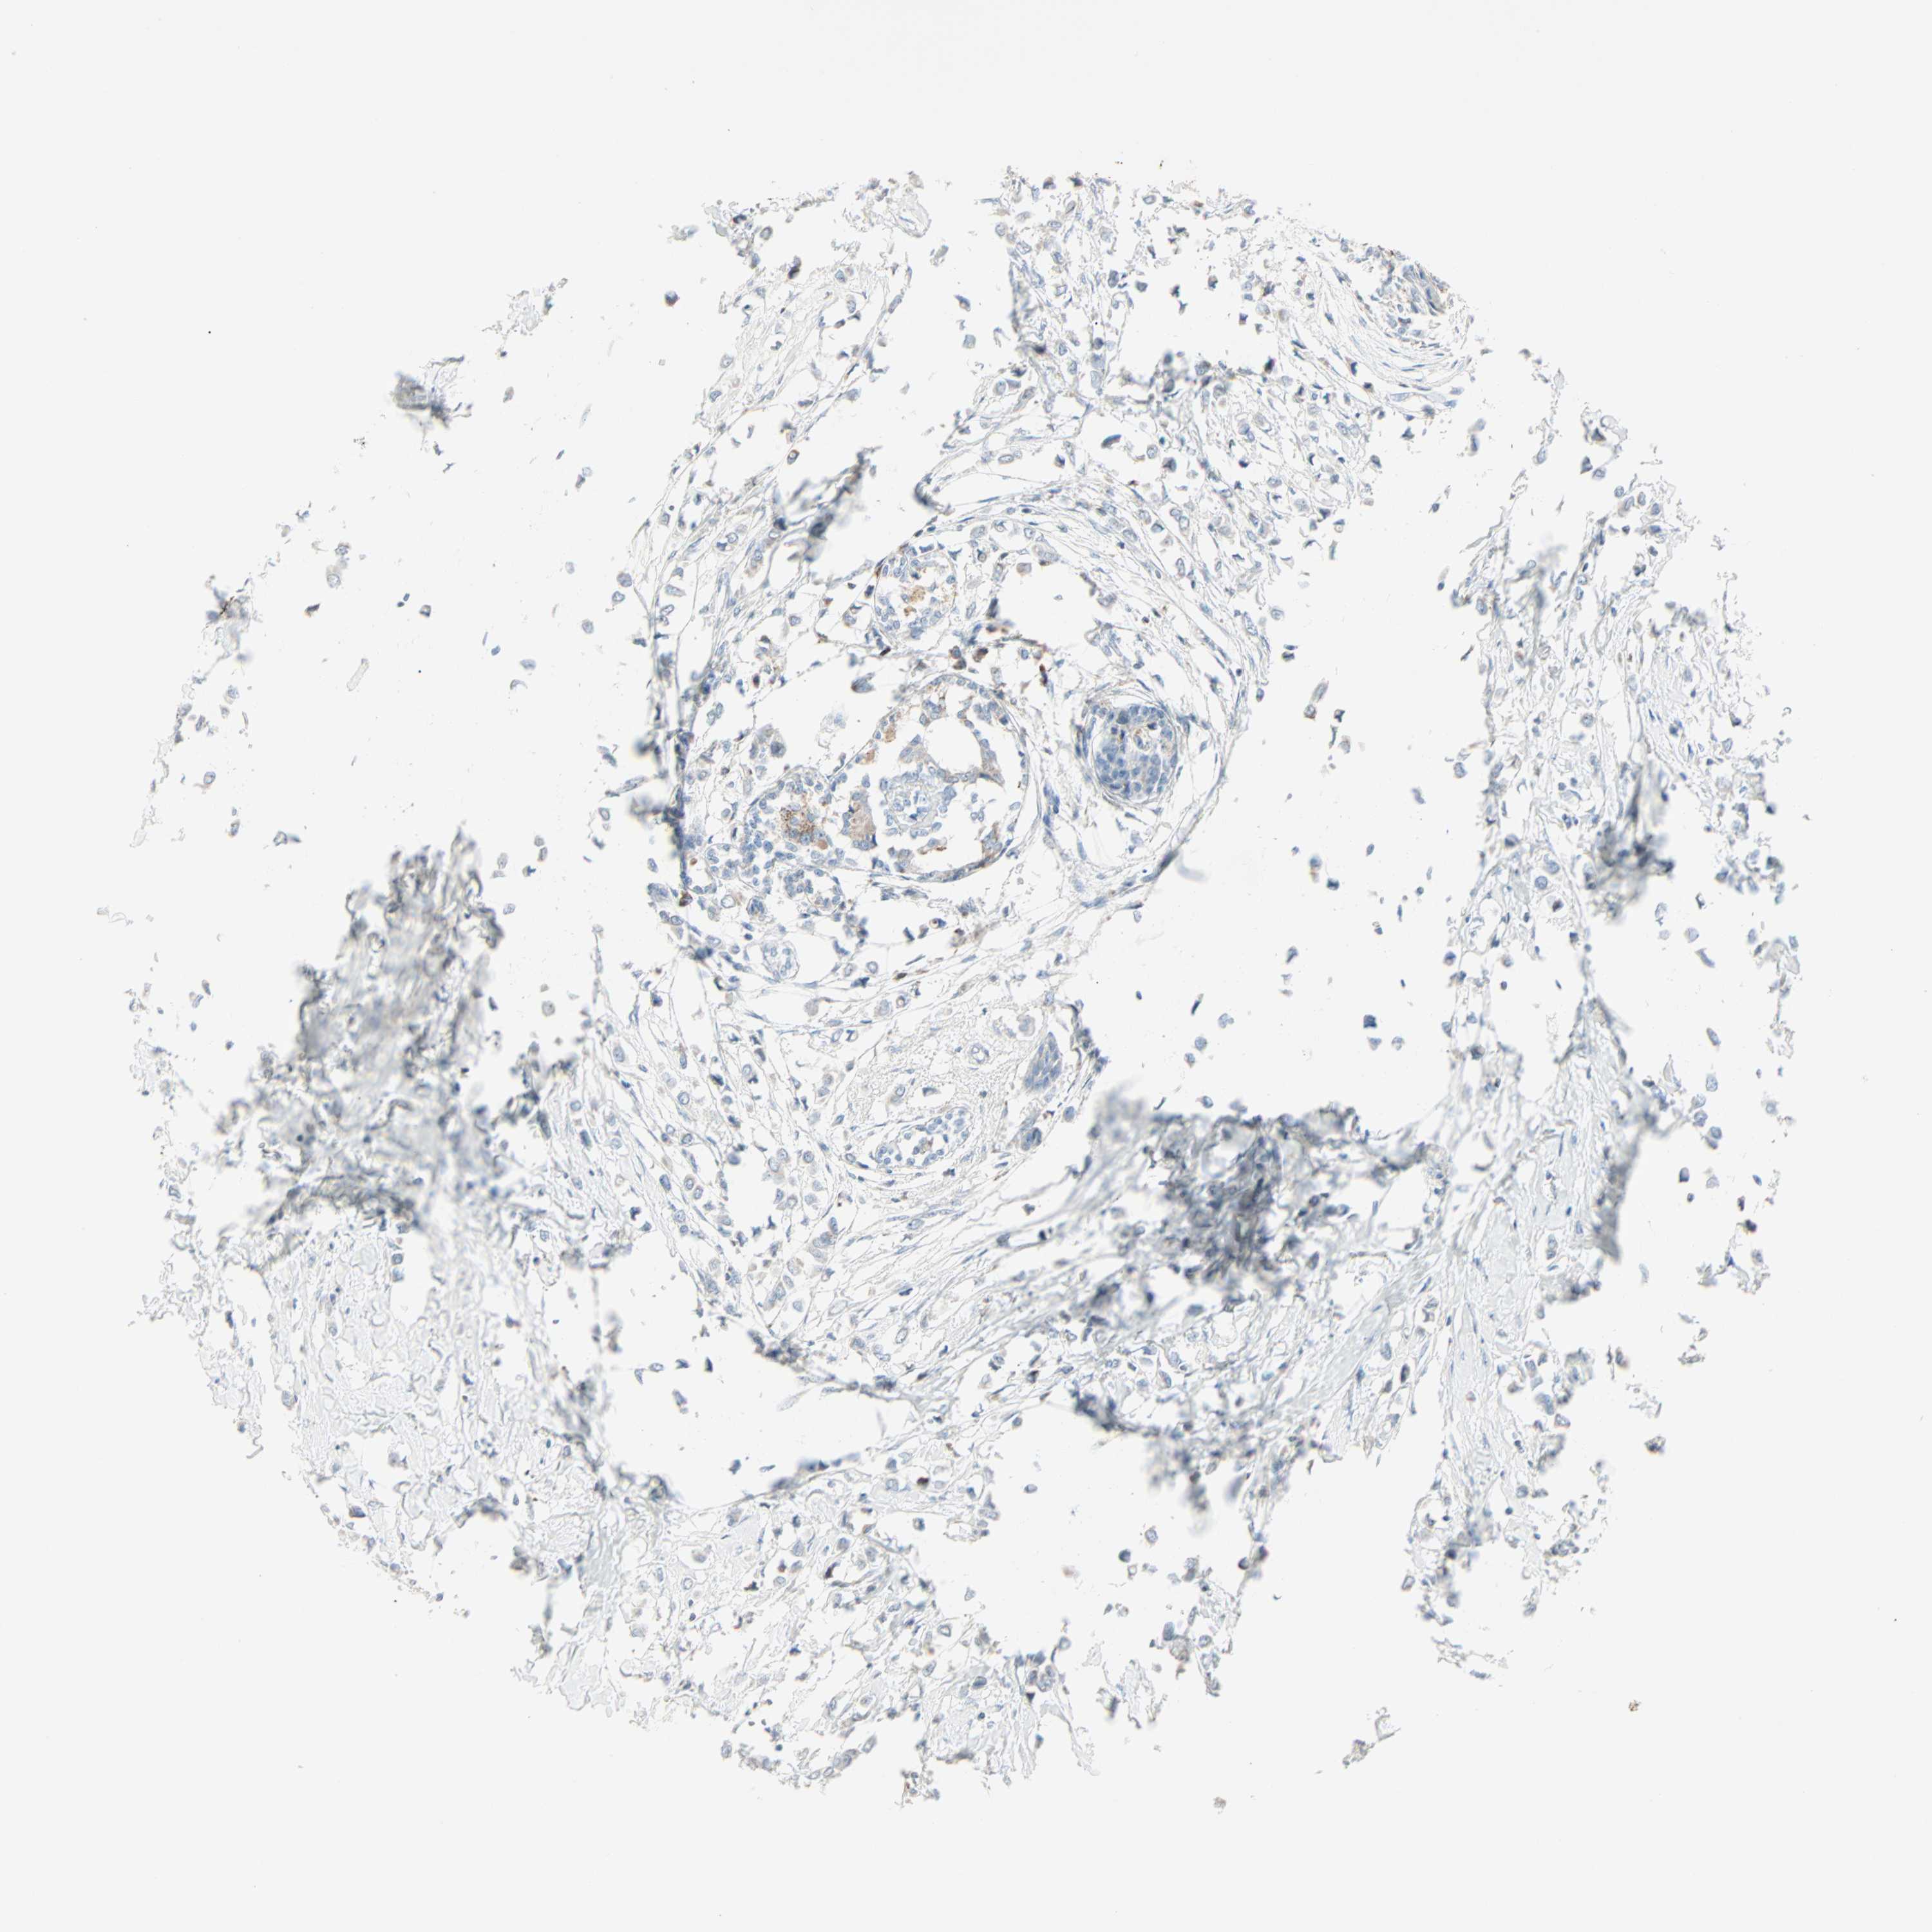

CANCER BREAST CANCER Show tissue menu

BRCA TCGA BRCA VALIDATION PROTEIN EXPRESSION

Breast cancer

Human cancer